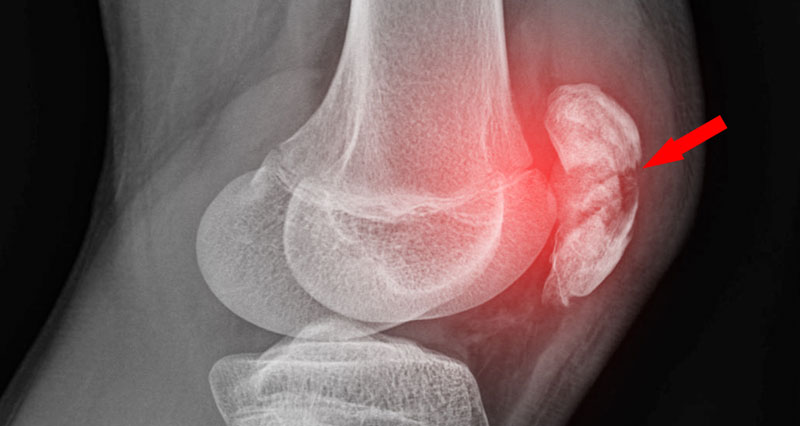

Patellar Fractures (Broken Kneecap

Patellar Fractures (Broken Kneecap

Patella Fracture | Reno Orthopedic Center direct fall on knee cap

patella hairline fracture? - Quora direct fall on knee cap